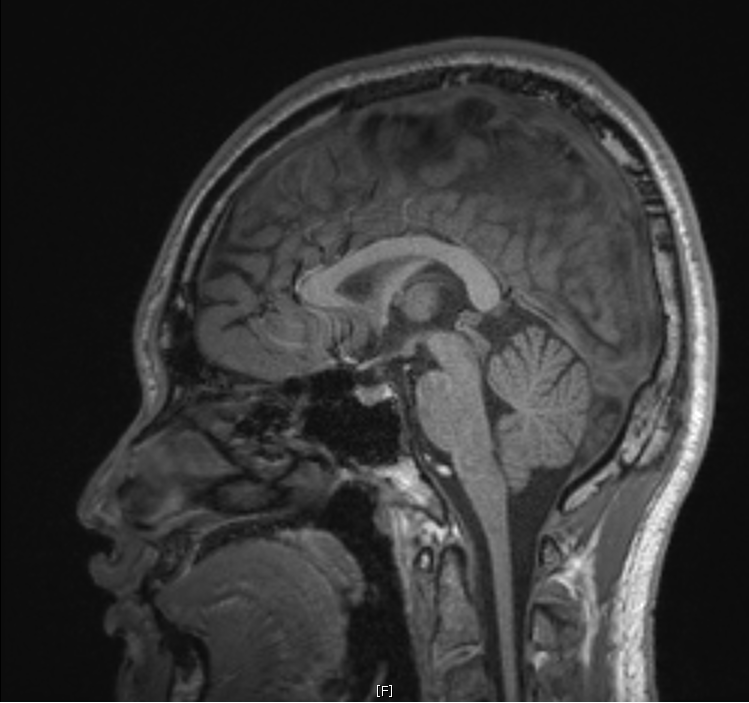

지난 금요일에 MRI를 촬영했는데요

혈관같기도 하고 하얀색 붕붕 뜨는 게 있어보이는데 (혈관같음)

한번 봐주실수 있나요? 그리고 전체적으로 괜찮은지도 봐주시면 감사하겠습니다.

특별하게 눈에 띄는 병변은 있어보이지 않습니다

말씀하신 것은 혈관의 가능성이 높겠습니다